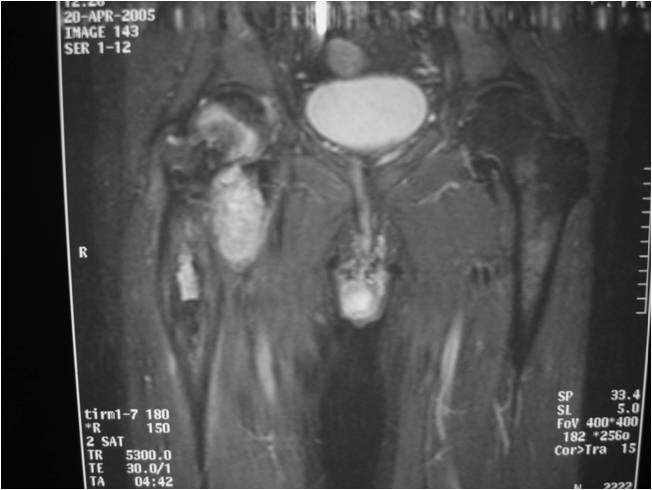

Radiographic Presentation

Radiology emulates pathology: Biphasic Tumor

- One region low grade chondrosarcoma

- Second more aggressive area with bone destruction, lysis of calcification, soft tissue mass

- Cortical permeation and a soft tissue mass in 70% of cases

Ill-defined, lytic intraosseous lesion

- Or extraosseous soft tissue mass

- Devoid of calcifications in continuity with lesions having the features of a cartilaginous tumor

Characteristically abrupt transition between chondroid tumor and dedifferentiated, lytic component

Bone may be expanded and adjacent cortex thickened

(Right Arrow)Aggressive Lytic Area (Dedifferentiated Sarcomatous Component) Cortical Destruction Soft Tissue Mass without Calcification